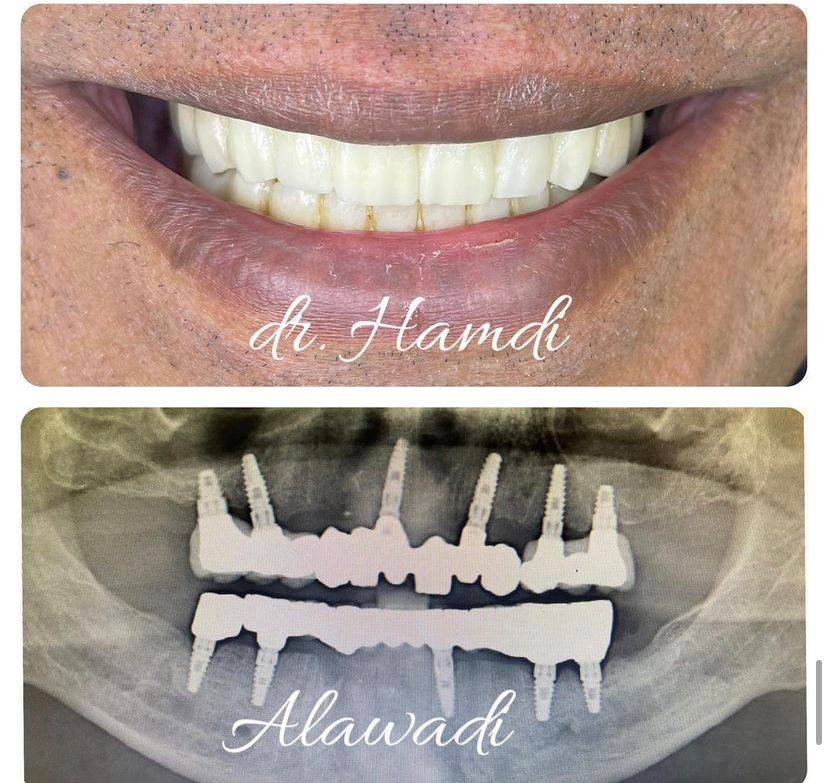

الدكتور حمدي العوضي

تخرج الدكتور حمدي العوضي من كلية طب الأسنان في عام 2003 ، وأنهى فترة تدريبه ، وعمل على الفور في مستشفى اليمامة (وزارة الصحة) حيث عمل كممارس أسنان عام لمدة 4 سنوات.

أجرى الدكتور حمدي العوضي أكثر من 50.000 عملية زراعة أسنان وترقيع عظمي خلال السنوات العشر الأخيرة من ممارسته.